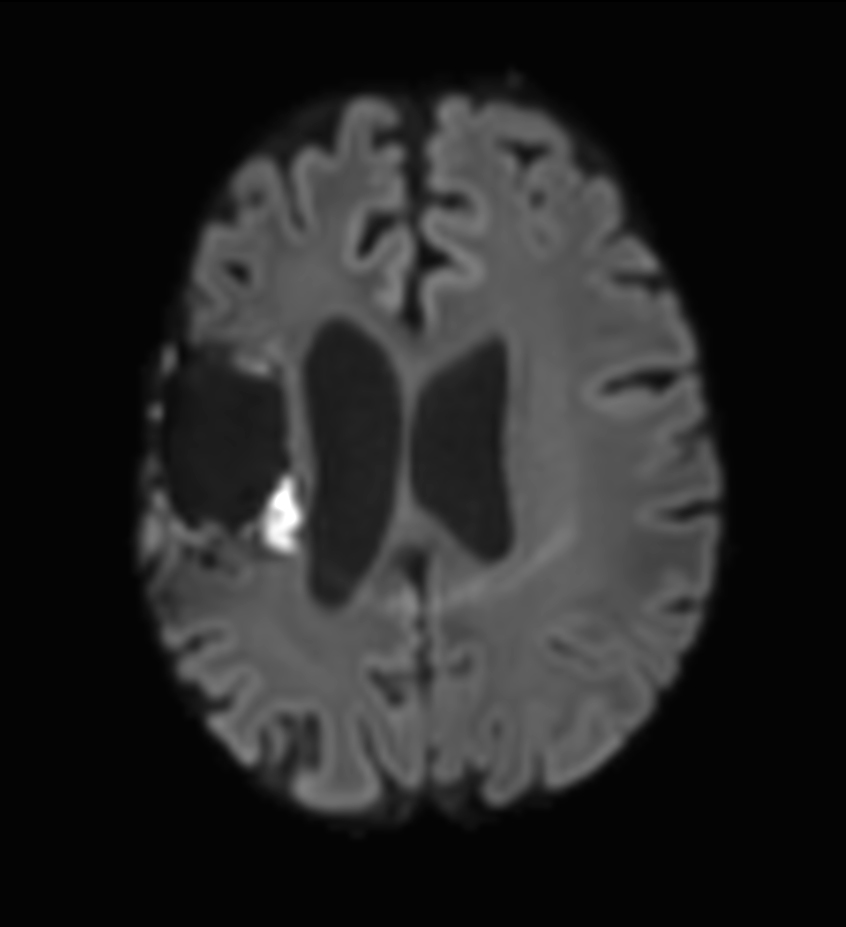

Brain glioblastoma, post-operative

Patient who was operated on glioblastoma

Axial DTI (b1000)

-